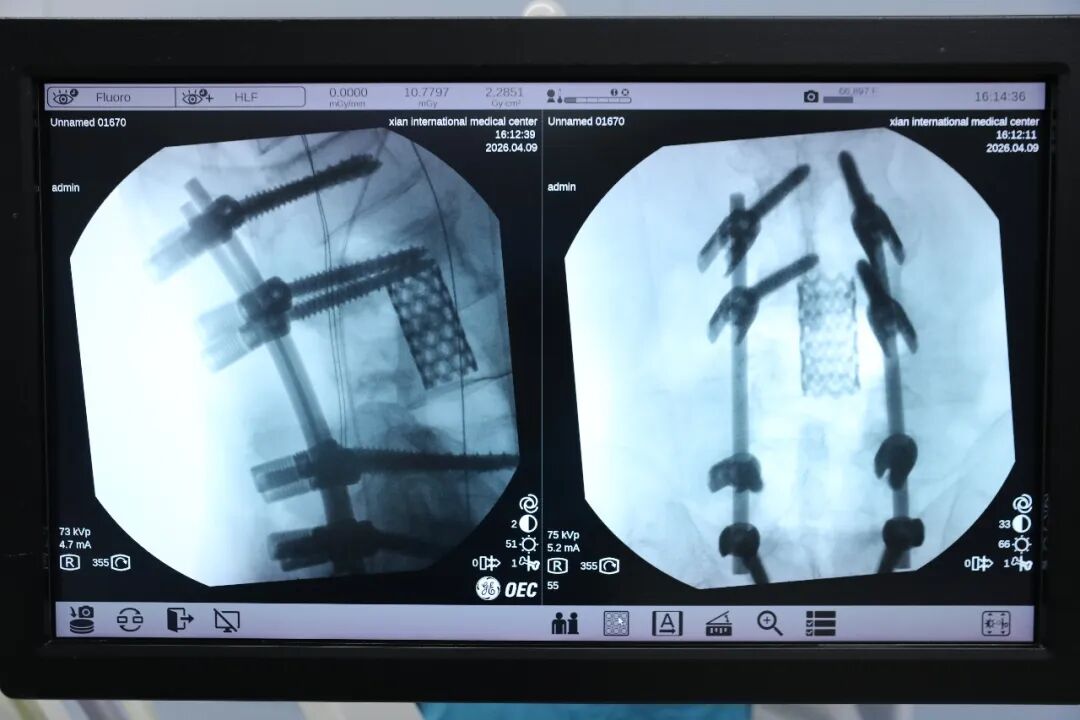

最关键的一步:重建被「挖空」的椎体。臧主任凭借精湛技术,在狭小空间内避开神经根分支,从后路将一枚充满自体骨和人工骨的钛笼,精准植入腰 3-4 椎体之间。随后用 8 枚椎弓根螺钉和连接棒,为这段「废墟」上的脊柱搭建了坚固的「桥梁」。

手术成功!术中出血控制在 1000 ml。术后病理报告揭晓谜底:放射性骨坏死。